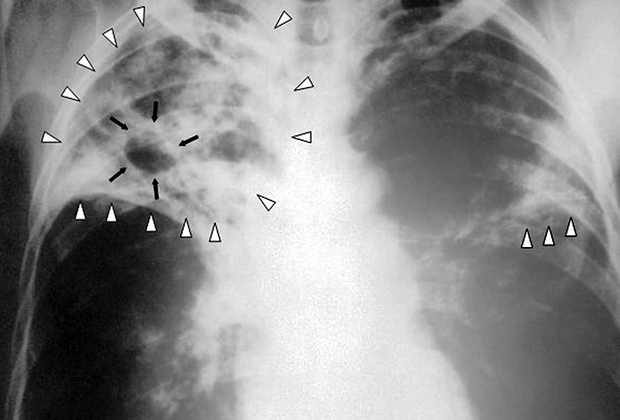

Медицинские аспекты заболеваний: рентгенологическая картина туберкулеза костей

Раздел: Снимки-откровения